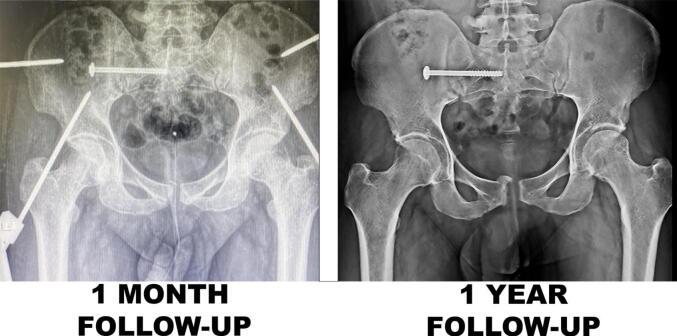

Delayed presentation of closed APC type III pelvic ring injury with a healing wound on the medial thigh, in a twenty-six-year-old male, at four weeks. We planned Symphyseal plating and sacroiliac screw fixation surgery. After percutaneous screw fixation, subsequent pelvic exposure revealed whitish cheesy pus in the retropubic space. Hence, we changed surgery from internal fixation to a supra-acetabular external fixator. Subsequent molecular testing documented tuberculosis and regimen of antitubercular medications was started. Complete functional recovery was observed at 12 months. While managing pelvic injuries, alternative backup treatment plans should be kept ready in view of infective foci.

一名26岁男性在四周时出现闭合性APC III型骨盆环损伤延迟就诊,大腿内侧有愈合伤口。我们计划行耻骨联合钢板固定和骶髂螺钉固定手术。经皮螺钉固定后,随后的骨盆暴露显示耻骨后间隙有白色干酪样脓液。因此,我们将手术从内固定改为髋臼上外固定架。随后的分子检测证实为结核病,并开始了抗结核药物治疗方案。12个月时观察到完全功能恢复。在处理骨盆损伤时,鉴于感染灶,应随时准备好替代的备用治疗方案。